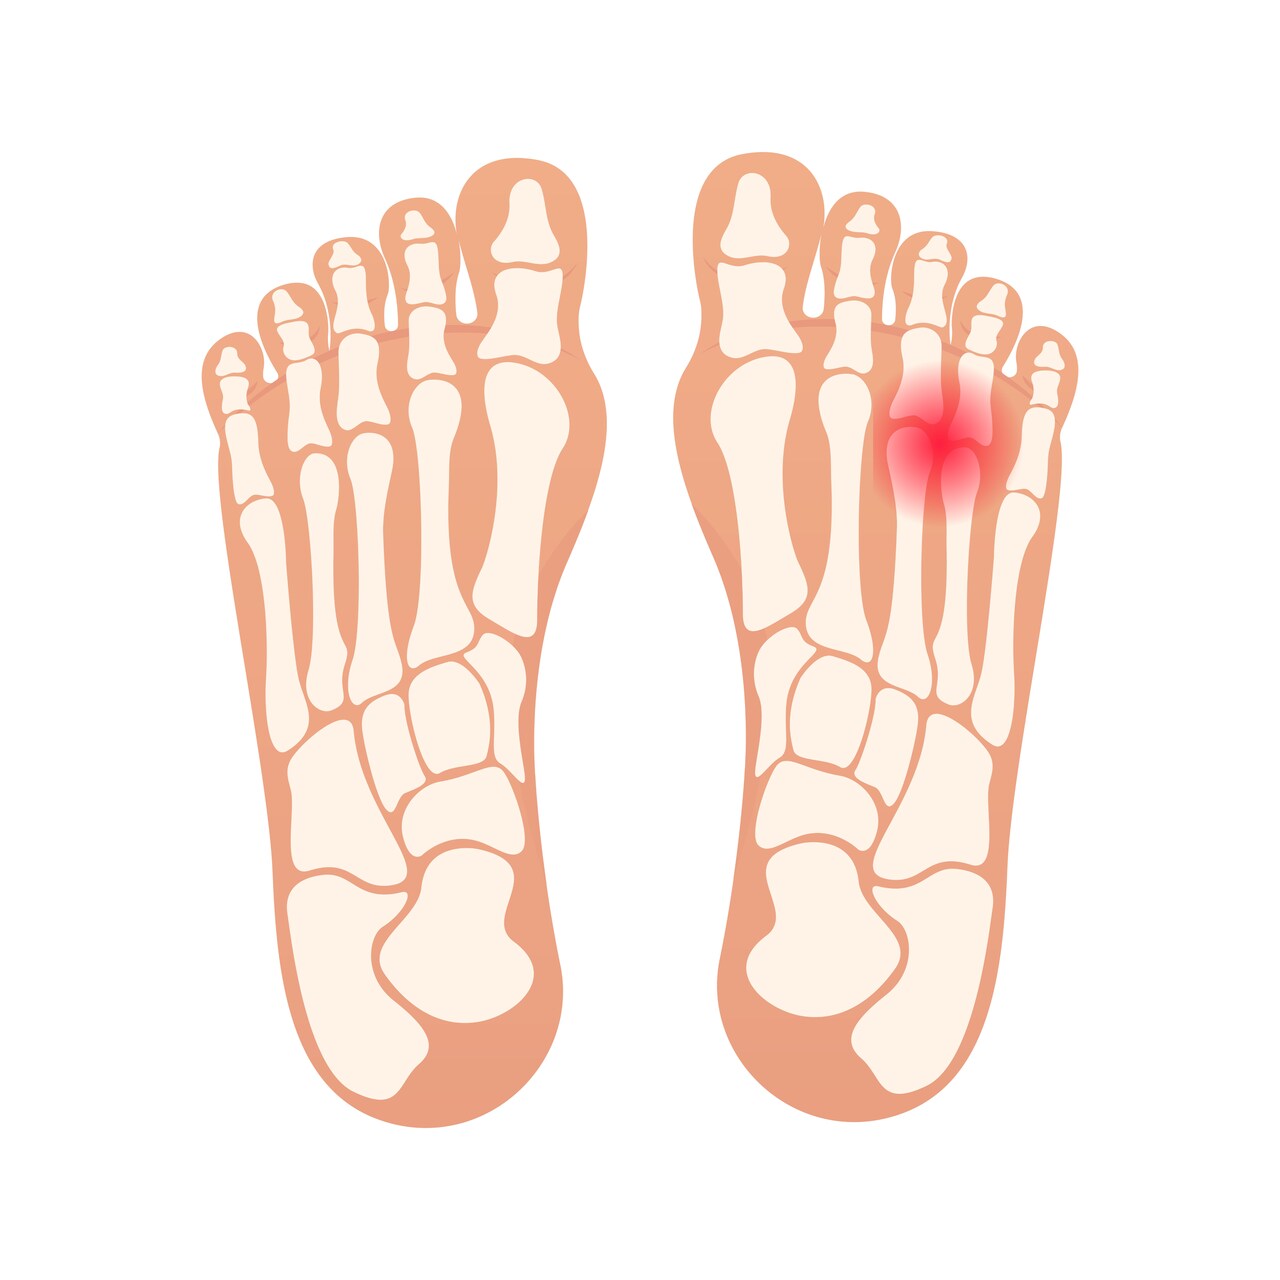

O neuroma de morton é uma doença que afeta os pés, causando uma inflamação do nervo sensitivo do terceiro e quarto dedos. O trauma repetitivo, pressão excessiva nos pés por calçados de solado duro e os desequilíbrios biomecânicos podem favorecer o aparecimento do neuroma.

• Dor no pé que piora ao caminhar ou praticar exercícios físicos;

• Queimação no terceiro e quarto dedos.

• Sensação de estar pisando em pedra.